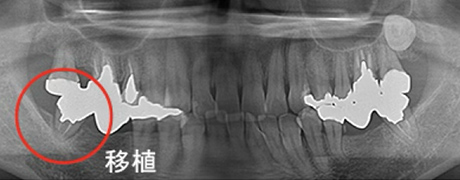

歯牙移植(骨の移植)

むし歯や歯周病で歯を失った後に、通常必要のない親知らずを、なくなった箇所に移植することによって健康な歯並びを回復する事ができます。

※移植には適合のための条件があります。